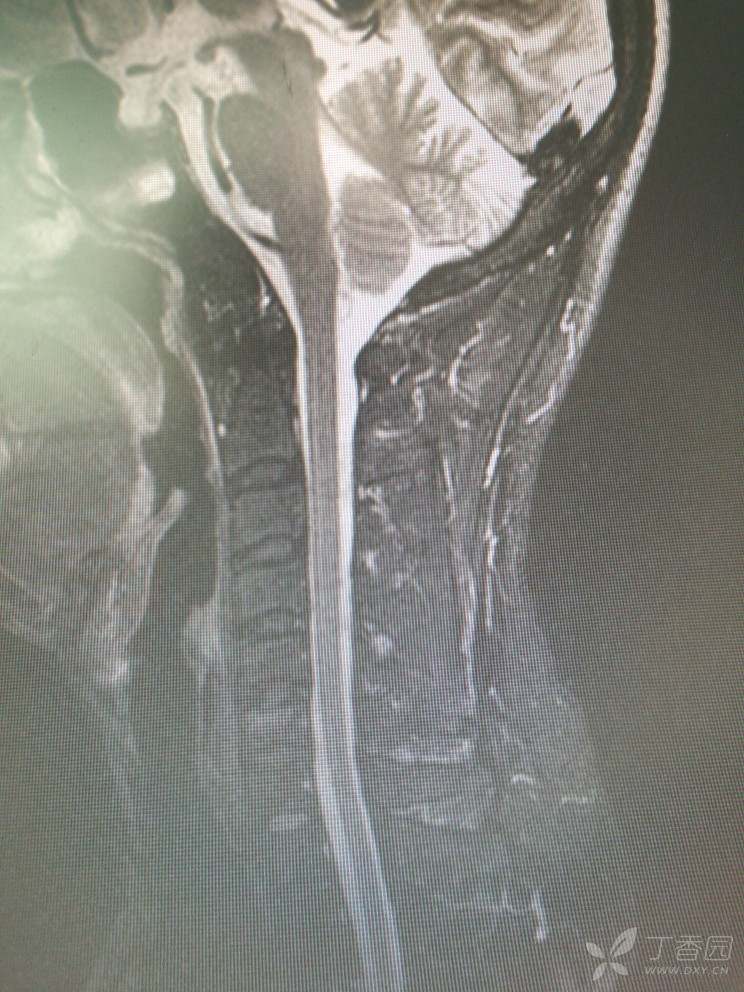

入院查MRI

我想问还是考虑L4/5 L5/S1椎间盘的变性引起的吗?